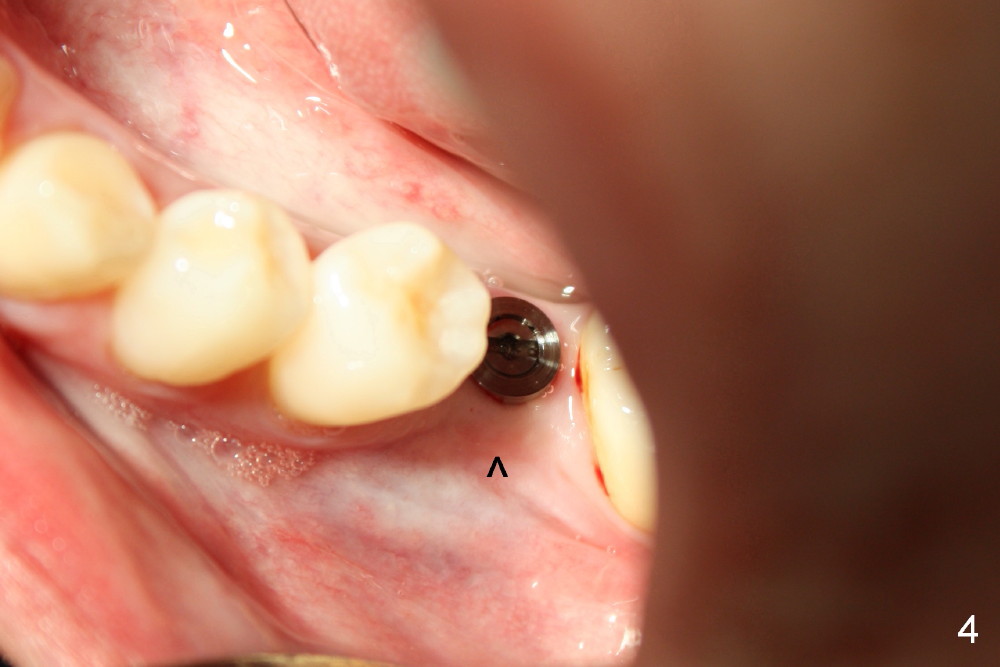

植牙不太容易,由于骨质缺损,植牙小些:4.5x17 mm,可能够用。几个月后病人回来,植牙愈合正常(图三,四,不过颊侧骨质凹陷,箭头),预约几周后修复。当她再回来做修复时,突然主述左上第一磨牙疼痛,需要做根管治疗,牙冠,老公满口同意,这时我们可以吃豆腐了(左上做牙冠,解决那里牙齿过分萌出问题(supraeruption)),不知他们这时怎么那么感慨解囊。